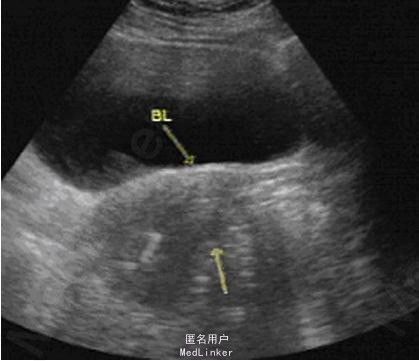

女性,42岁,上环15年。

【影像表现】 后位子宫,大小形态正常,包膜光整,实质回声均匀,宫内见节育环回声,位置正常。CT扫描示子宫大小及形态未见明显异常,肌层密度均匀,宫腔内可见一节育环密度影,位置未见异常。

【诊断】 宫腔内节育环 【鉴别诊断】 宫腔内异物

【讨论】子宫内放置节育器是最简单有效的避孕方法,节育器有多种形状,国内以金属圆形单环最多见,其次为“T”形及花瓣状。 1.影像诊断要点:① 盆腔X线透视及平片可对其位置和形状做出准确的诊断;② 超声检查可见宫腔内强回声节育环回声;③ CT检查可见宫腔内的金属密度节育环影,以上几种检查都可对节育环的位置及形状做出准确的诊断。 2.鉴别诊断:主要与宫腔内异物及钙化鉴别,后者多为形态不规则或有特定形态,结合临床病史即可做出鉴别诊断。